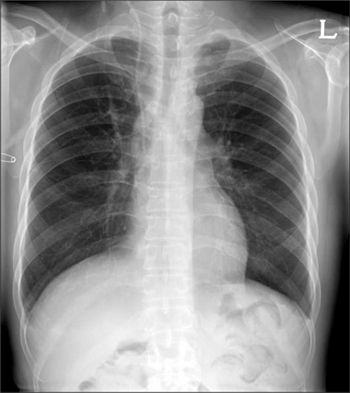

Флюорографію проводять з метою виявлення патологій органів дихання у дорослої людини. За Російським законодавством дослідження проводять з 15-річного віку, при наявності показань (затяжний кашель, що супроводжується трудноотделяемой мокротою і болем в грудей). Даний метод обстеження є добровільним, і ніхто не має права примушувати вас проходити флюорографію.

Доцільніше дітям проводити ультразвукове дослідження або рентгенологічне. Шкоду, що завдається дитячому організму від даних процедур, в рази менше, ніж від флюорографії. Тому флюорографічне дослідження дітям не роблять. Багато хто запитає – чому?

- Рентгенографію;

- Рентген органів грудної клітки.